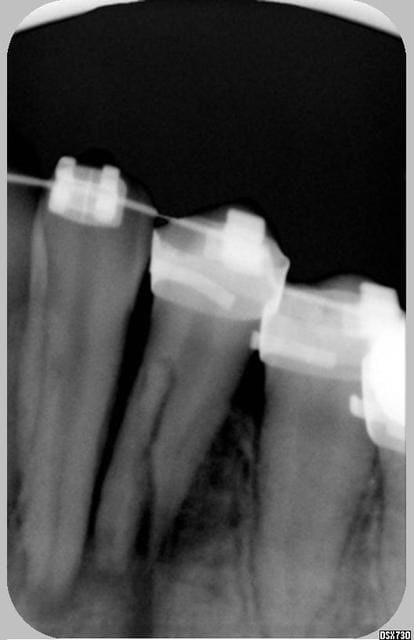

Pour mettre un peu de polémique, voici le résultat d'une chirurgie fait par un ponte parisien. Texto au téléphone : "J'opère couramment des becs de lièvre (il est vrai que ses réultats sont impressionnants), la chirugie mandibulaire ne doit pas être compliquée "

Il a prélevé de l'os au niveau du tibia. Ce qui gêne encore aujourd'hui.

Il y a actuellement lyse radiculaire de bloc incisivo-canin et aucune sensibilité de ce groupe.

Il a été condamné pour ses actes. Il est médecin et doit savoir ligaturer une carotide.

C'est clair c'est un Obwegeiser-DalPonte ...dentaire :-)